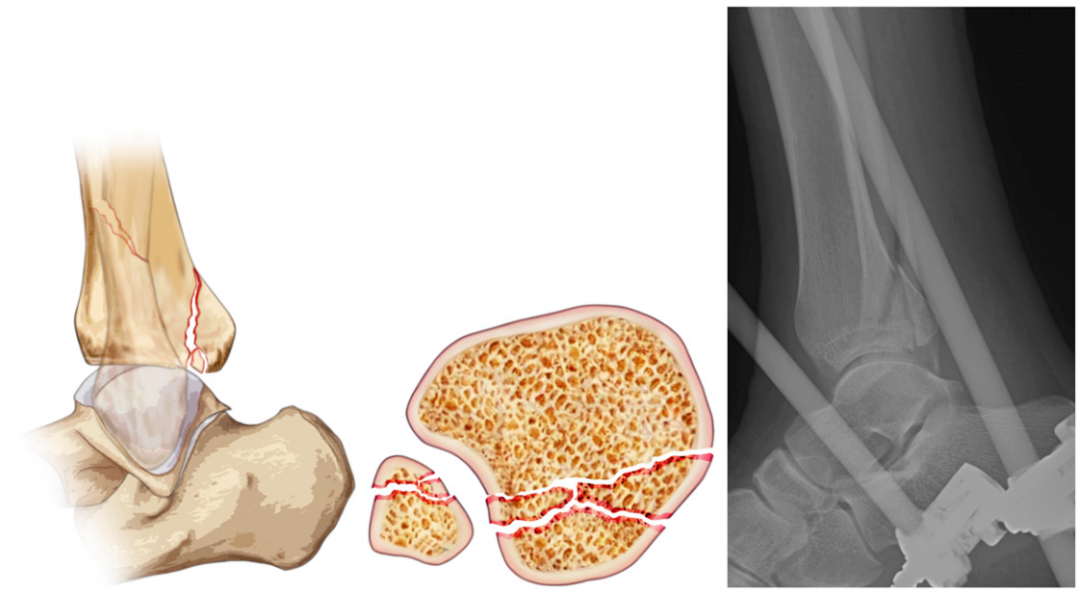

后Pilon骨折

由高能轴向压缩损伤(如高处坠落)引起,累及整个胫骨远端后侧穹顶,包括后柱和内侧柱。骨折常表现为粉碎性和关节面压缩,类似典型胫骨Pilon骨折但局限于后侧,多由轴向负荷(如垂直压缩)导致。CT检查显示广泛关节面压缩、骨折块较大,且常累及胫骨后柱和内侧柱,骨折块面积比等参数较后踝骨折更显著,通常归类为AO/OTA 43-C 型。由于软组织损伤严重,通常需要分期手术治疗:先进行外固定,再实施钢板内固定。

▲图示为后Pilon骨折,包含踝关节侧位视图、踝关节轴位视图,以及踝关节侧位影像。